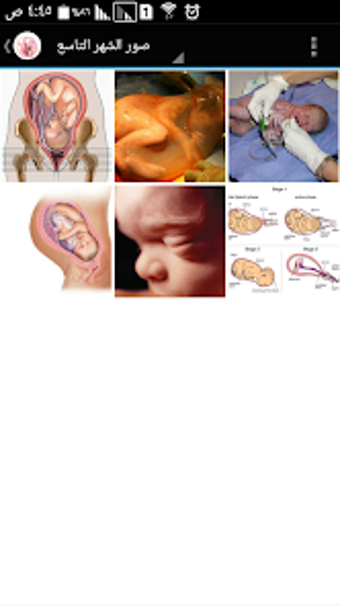

The Pregnancy and Birth Calculator App by metraqapps is a free Android utility tool app designed for expecting mothers. This app provides an extensive guide to pregnancy, including a month-by-month breakdown of fetal development, symptoms, and tips for a healthy pregnancy. The app also includes a pregnancy calculator to determine the due date and a contraction timer to help track labor.